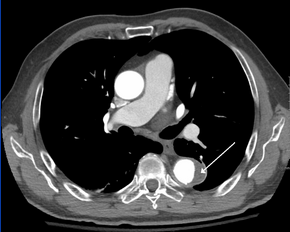

Computed tomography angiography is a fast, noninvasive test that gives an accurate three-dimensional view of the aorta. These images are produced by taking rapid, thin-cut slices of the chest and abdomen, and combining them in the computer to create cross-sectional slices. To delineate the aorta to the accuracy necessary to make the proper diagnosis, an iodinated contrast material is injected into a peripheral vein. Contrast is injected and the scan performed using a bolus tracking method. This type of scan is timed to an injection to capture the contrast as it enters the aorta. The scan then follows the contrast as it flows through the vessel. It has a sensitivity of 96 to 100% and a specificity of 96 to 100%. Disadvantages include the need for iodinated contrast material and the inability to diagnose the site of the intimal tear.

CT with contrast demonstrating aneurysmal dilation and a dissection of the ascending aorta (type A Stanford)

Chest CT with descending (type B Stanford) aortic dissection (red circle)

Type A dissection with pericardial effusion as a result.